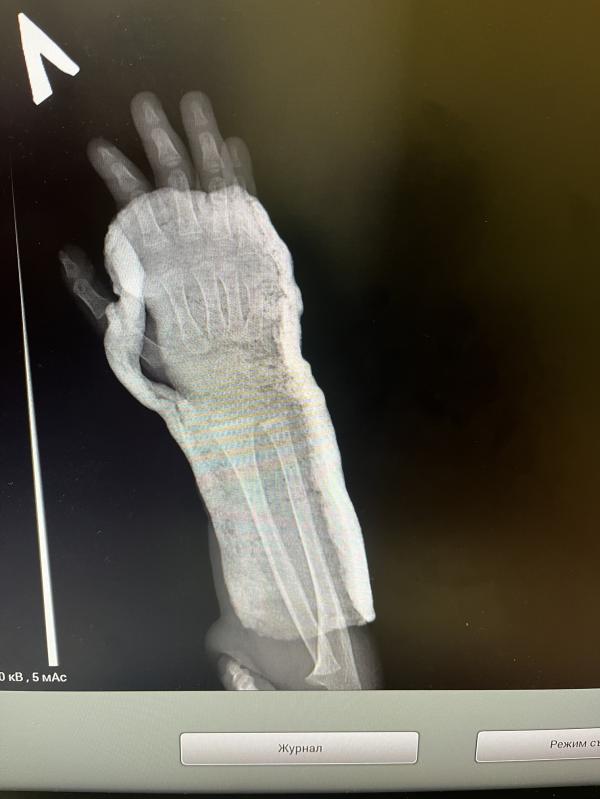

Зачем делать рентген в гипсе, если ничего не видно?

Скажите, зачем делать рентген в гипсе, если ничего не видно 🤪

До пятницы ждать , снимут и еще отфоткают .. ждем

Проверяют как срастается. Нет ли смещения. Иногда нужно гипс переделать. В общем для контроля ситуации

Но ведь врач в итоге ничего не увидел в гипсе(